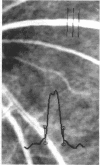

Accurate determination of retinal vessel width measurement is important in the study of the haemodynamic changes that accompany various physiological and pathological states. Currently the width at the half height of the transmittance and densitometry profiles are used as a measure of retinal vessel width. A consistent phenomenon of two 'kick points' on the slopes of the transmittance and densitometry profiles near the base, has been observed. In this study, mathematical models have been formulated to describe the characteristic curves of the transmittance and the densitometry profiles. They demonstrate the kick points being coincident with the edges of the blood column. The horizontal distance across the kick points would therefore indicate the actual blood column width. To evaluate this hypothesis, blood was infused through two lengths of plastic tubing of known diameters, and photographed. In comparison with the known diameters, the half height underestimated the blood column width by 7.33% and 6.46%, while the kick point method slightly overestimated it by 1.40% and 0.34%. These techniques were applied to monochromatic fundus photographs. In comparison with the kick point method, the half height underestimated the blood column width in veins by 16.67% and in arteries by 15.86%. The characteristics of the kick points and their practicality have been discussed. The kick point method may provide the most accurate measurement of vessel width possible from these profiles.